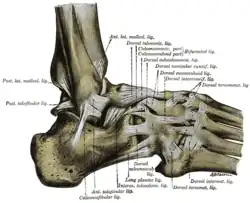

Большеберцовая и малоберцовая кости охватывают блок таранной кости наподобие вилки. Суставная капсула сзади и по бокам прикрепляется к краям сочленяющихся поверхностей, а спереди на полсантиметра отступает от них. Связки располагаются на боковых поверхностях сустава[3]:

- На внешней стороне сустава расположены передняя и задняя таранно-малоберцовые и пяточно-малоберцовая связки — все они расходятся веерообразно, начинаясь на латеральной лодыжке: передняя таранно-малоберцовая связка (лат. ligaméntum talofibuláre antérius) крепится к шейке таранной кости, задняя таранно-малоберцовая связка (лат. ligaméntum talofibuláre postérius) — к заднему отростку таранной кости, а пяточно-малоберцовая связка (лат. ligaméntum calcaneofibuláre) спускается вниз, оканчиваясь на наружной поверхности пяточной кости.

- На внутренней стороне голеностопного сустава расположена дельтовидная (медиальная) связка (лат. ligaméntum deltoídeum seu mediále), которая начинается на внутренней (медиальной) лодыжке и делится на четыре части:

- большеберцово-ладьевидная часть (лат. pars tíbionaviculáre) прикрепляется к ладьевидной кости стопы;

- большеберцово-пяточная (лат. pars tíbiocalcánea) крепится к пяточной кости;

- передняя и задняя большеберцово-таранные части (лат. pártes tíbiotaláres antérior et postérior), прикрепляющиеся к таранной кости.